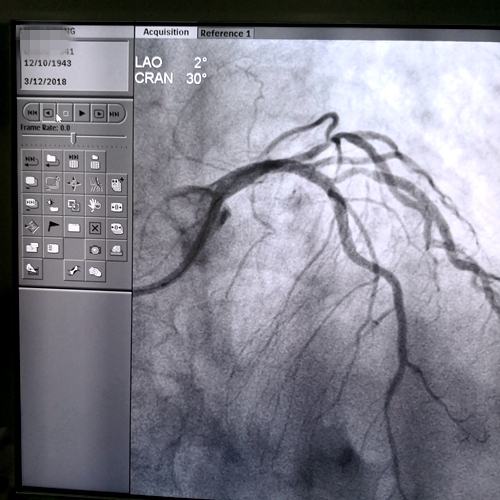

术后造影

廖奶奶目前已行冠脉造影示:右冠慢性完全性闭塞,左前降支近段次全闭,并在病变处植入支架,开通血管,症状也就基本消失了。